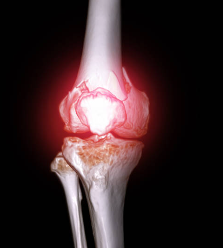

1. 내측 인대 손상

내측 인대는 무릎 안쪽에 있는 인대로, 무릎을 안정시키고 관절의 움직임을 조절하는 역할을 합니다. 내측 인대가 늘어나거나 찢어지면 무릎 안쪽 통증이 발생하며, 부기, 멍, 무릎의 불안정감 등의 증상이 동반될 수 있습니다. 내측 인대 손상은 스포츠 활동 중에 다리를 외반시키거나 무릎을 과도하게 굽히는 경우에 자주 발생합니다.